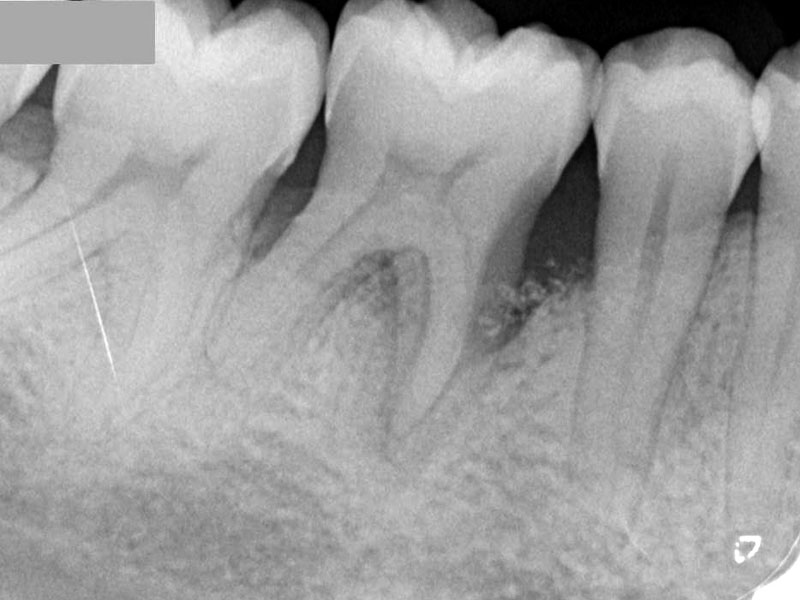

06/08 - Pre-operative radiographRegeneration at LR6 with cerabone® and collprotect® membrane using simple papilla preservation technique - Dr. D. Chatzopoulou